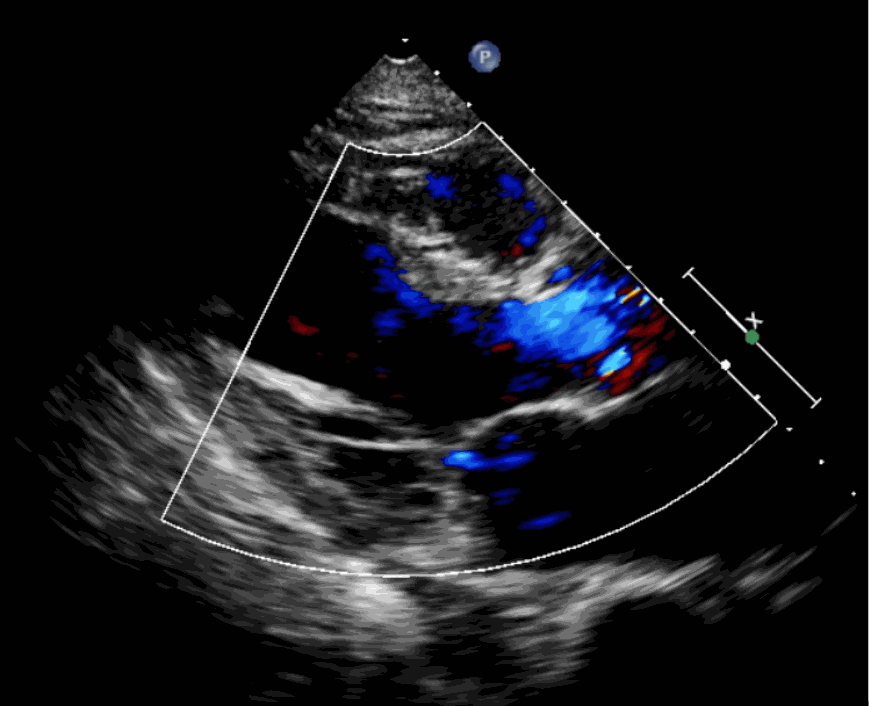

術(shù)后超聲影像圖